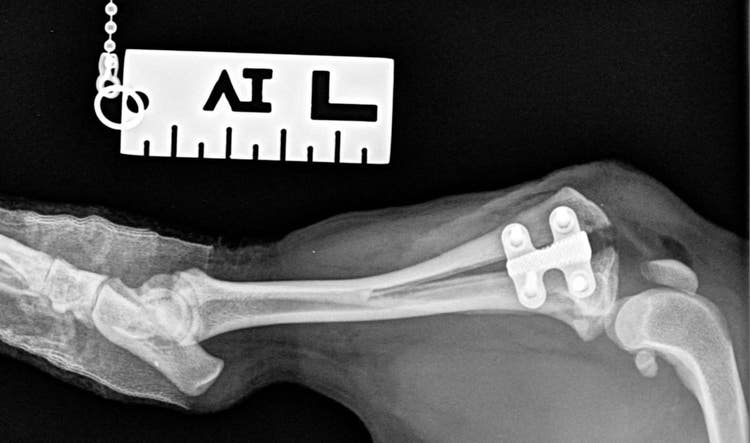

New research led by Orthopaedic Specialist Steve Butterworth at CVS’ Weighbridge Referral Centre, Swansea has found that tibial tuberosity advancement (TTA)-Rapid, a popular technique to treat cruciate ligament rupture in dogs, offers a good medium to long-term treatment outcome for canine cranial cruciate ligament failure - even in patients with tibial plateau angles of greater than 30⁰.

TTA is a popular surgical procedure to treat dogs showing lameness associated with CCLI. Though past research has highlighted satisfactory short (6-12 weeks)[ii] and medium (mean 16 months)[iii] term outcomes, there is limited research on a longer (>16 months) follow-up periods. It has also been speculated that dogs with tibial plateau angles (TPA) of greater than 30⁰ are not well suited for a TTA[iv].

The researchers concluded that the long-term (median of 37.5 months) outcome for dogs undergoing TTA-Rapid for cranial cruciate ligament disease is satisfactory, with no risk factors associated with poorer outcomes identified. Their study also revealed no evidence to support the suggestion that dogs with TPAs of greater than 30◦ may be inappropriate candidates for TTA - after testing several parameters to judge outcome including frequency of lameness, severity of lameness, distance walked daily and mobility score.